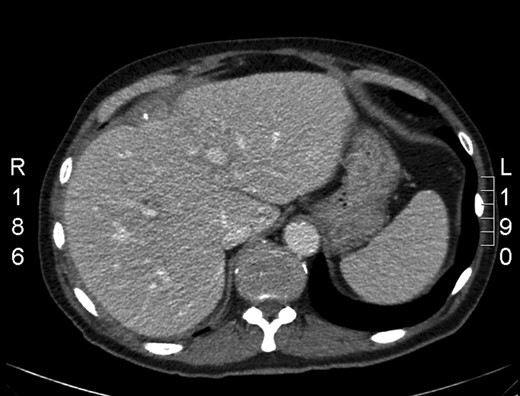

He presented 6 weeks later complaining of right upper quadrant pain and fever. He had a raised white cells count of 15 and an elevated C-reactive protein (CRP) of 110. A computer tomography (CT) abdomen (Fig. 1) was performed, which showed numerous calcific densities that were surrounded by soft tissue thickening and stranding. These were likely spilled stones. There was no evidence of collection. He was admitted for 2 days on Intravenous (IV) antibiotics then discharged.